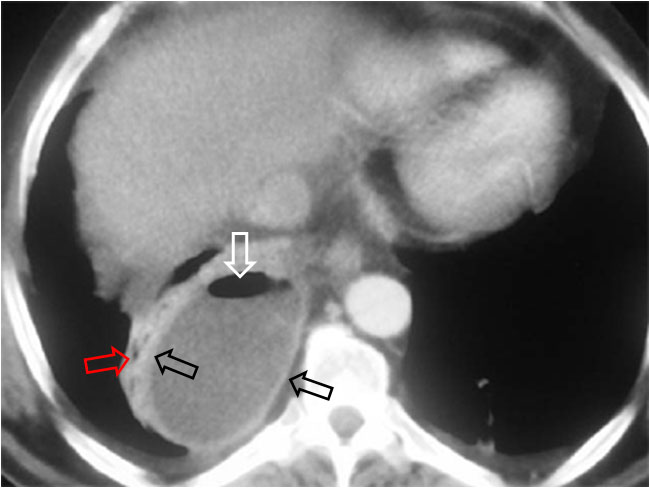

Es un signo de empiema en la TC de tórax con contraste intravenoso. El signo consiste en el despegamiento de ambas hojas pleurales, que muestran un engrosamiento liso difuso y un realce con la administración de contraste. La imagen muestra la pleura visceral (flecha superior) y la pleura parietal (flecha inferior) despegadas. Ambas hojas se unen en los márgenes de la colección.

Otro ejemplo de este signo. El empiema muestra el despegamiento de las hojas pleurales visceral y parietal (flechas negras). Además, puede verse gas dentro del empiema (flecha blanca) y pulmón colapsado adyacente a la colección (flecha roja).